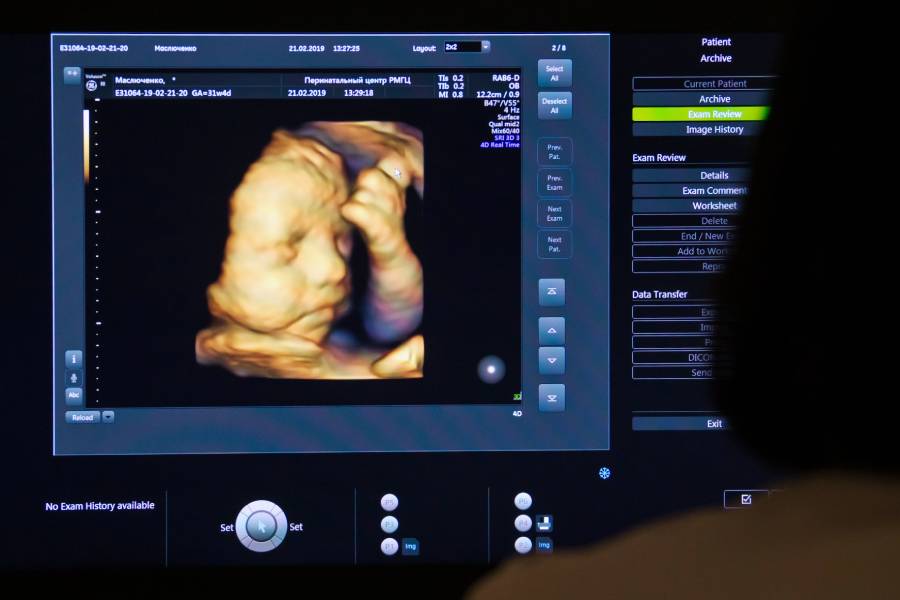

На сегодняшний день оборудование для УЗИ значительно улучшилось, однако в некоторых клиниках всё ещё используют устаревшие аппараты, что значительно снижает качество диагностики. Современные ультразвуковые сканеры обладают высоким разрешением, многофункциональностью и возможностью трёхмерной визуализации, что помогает получить максимально точное изображение.

Если в лаборатории или клинике применяют старую технику, существует риск упущения деталей или неправильной оценки состояния. Например, при скрининге плода в первом триместре важно точно определить наличие аномальных особенностей, и качество изображения напрямую влияет на это.